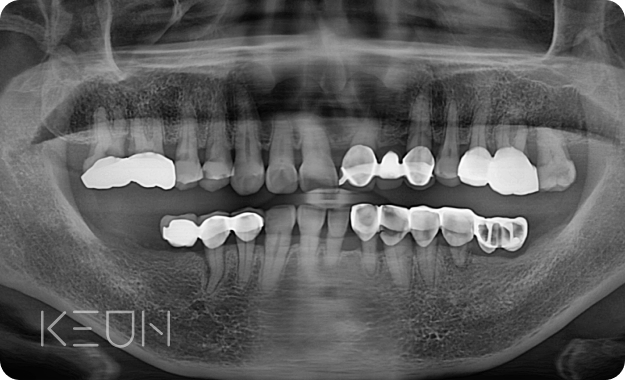

어르신 복합치료 전후사진.

- Before

- After